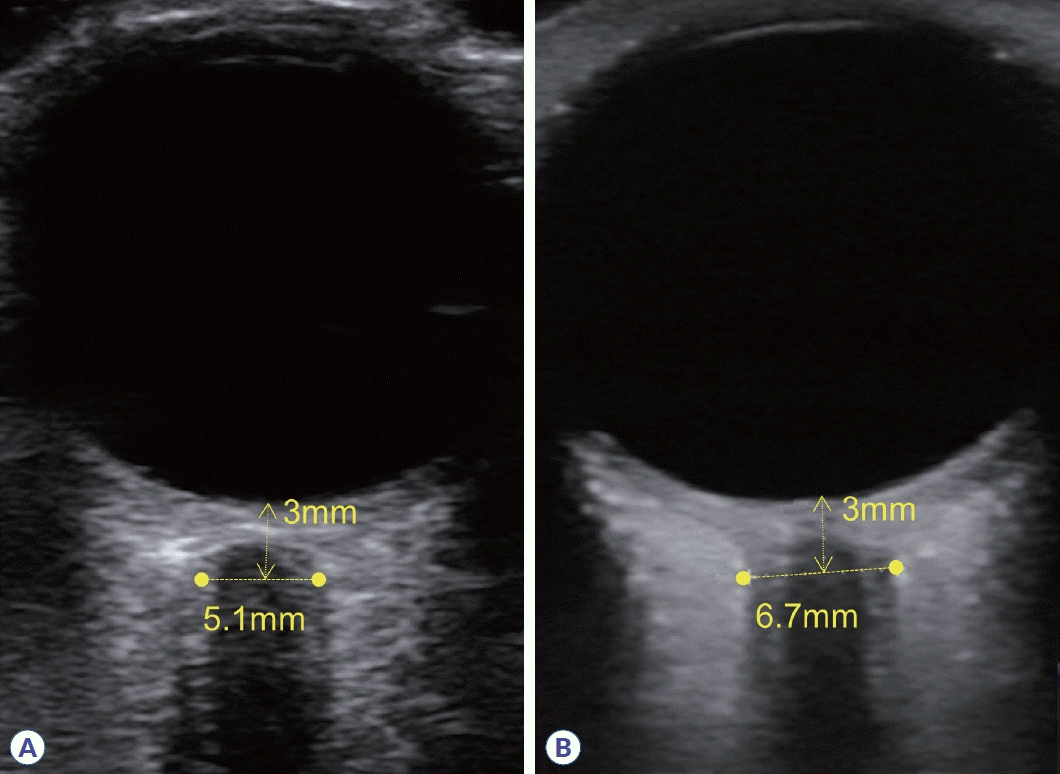

Figure 2.

Transocular ultrasonography findings in normal optic nerve (A) and optic neuritis (B). The optic nerve sheath diameter measured at a depth of 3 mm from the optic disc is thicker in optic neuritis compared to the normal optic nerve.